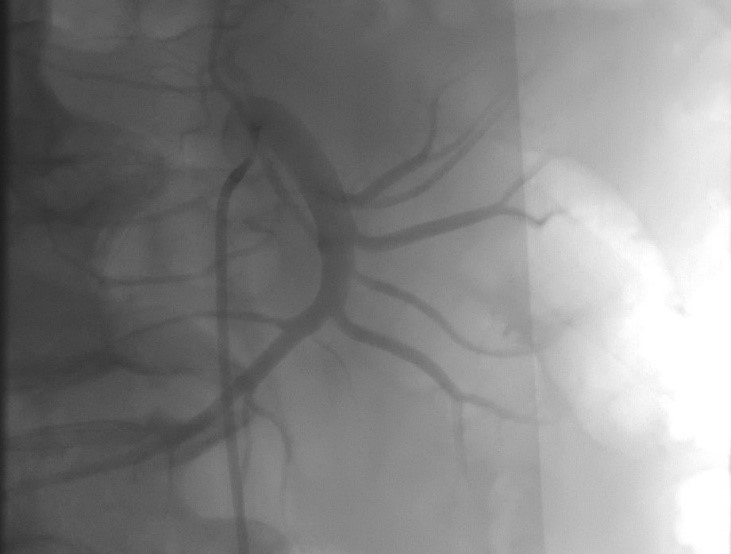

26.11.202 г. из правого бедренного доступа выполнена катетеризация правой бедренной артерии с последующей катетеризацией и эмболизацией нижней панкреатодуоденальной артерии дистальнее и проксимальнее аневризмы.

Рис. 4. Контрольная ангиография (визуализирована эмболизированная нижняя панкреатодуоденальная артерия).

Fig. 4. Control angiography (the embolized inferior pancreaticoduodenal artery is visualized).

При контрольной ангиографии — антеградного кровотока нет (рис. 4). В удовлетворительном состоянии пациент выписан 29.11.2021 г. на амбулаторное лечение. Спустя 1 год пациент полностью компенсирован по витальным функциям, периодически посещает врача терапевта с целью диспансерного наблюдения. 01.11.2022 г. пациент госпитализирован в «Адамант Медицинская Клиника» для выполнения плановой холецистэктомии по поводу хронического калькулезного холецистита. При расширенном предоперационном обследовании других отклонений от нормы, кроме холелитиаза, не было выявлено. При контрольной МСКТ органов брюшной полости визуализирована эмболизированная аневризма нижней панкреатодуоденальной артерии без признаков рецидива (рис. 5).